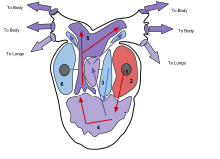

In humans, other mammals, and birds, the heart is divided into four chambers: upper left and right atria; and lower left and right ventricles.[4][5] Commonly the right atrium and ventricle are referred together as the right heart and their left counterparts as the left heart.[6] Fish in contrast have two chambers, an atrium and a ventricle, while reptiles have three chambers.[5] In a healthy heart blood flows one way through the heart due to heart valves, which prevent backflow.[3] The heart is enclosed in a protective sac, the pericardium, which also contains a small amount of fluid. The wall of the heart is made up of three layers: epicardium, myocardium, and endocardium.[7]

The heart functions as a pump in the circulatory system to provide a continuous flow of blood throughout the body. This circulation consists of the systemic circulation to and from the body and the pulmonary circulation to and from the lungs. Blood in the pulmonary circulation exchanges carbon dioxide for oxygen in the lungs through the process of respiration. The systemic circulation then transports oxygen to the body and returns carbon dioxide and relatively deoxygenated blood to the heart for transfer to the lungs.[7]

The right heart collects deoxygenated blood from two large veins, the superior and inferior venae cavae. Blood collects in the right and left atrium continuously.[7] The superior vena cava drains blood from above the diaphragm and empties into the upper back part of the right atrium. The inferior vena cava drains the blood from below the diaphragm and empties into the back part of the atrium below the opening for the superior vena cava. Immediately above and to the middle of the opening of the inferior vena cava is the opening of the thin-walled coronary sinus.[7] Additionally, the coronary sinus returns deoxygenated blood from the myocardium to the right atrium. The blood collects in the right atrium. When the right atrium contracts, the blood is pumped through the tricuspid valve into the right ventricle. As the right ventricle contracts, the tricuspid valve closes and the blood is pumped into the pulmonary trunk through the pulmonary valve. The pulmonary trunk divides into pulmonary arteries and progressively smaller arteries throughout the lungs, until it reaches capillaries. As these pass by alveoli carbon dioxide is exchanged for oxygen. This happens through the passive process of diffusion.

In the left heart, oxygenated blood is returned to the left atrium via the pulmonary veins. It is then pumped into the left ventricle through the mitral valve and into the aorta through the aortic valve for systemic circulation. The aorta is a large artery that branches into many smaller arteries, arterioles, and ultimately capillaries. In the capillaries, oxygen and nutrients from blood are supplied to body cells for metabolism, and exchanged for carbon dioxide and waste products.[7] Capillary blood, now deoxygenated, travels into venules and veins that ultimately collect in the superior and inferior vena cavae, and into the right heart.